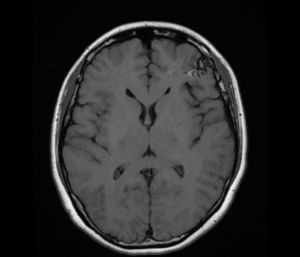

一名37岁女士被发现在家中晕倒、丧失意识,被送入公立医院。病人和家属获告知CT电脑扫描、脑电波图和所有血液化验结果一切正常,医生仍然没有临床线索来确定她晕厥的原因。于是病人出院后咨询脑血管外科医生意见,医生审查公立医院的血液检查报告时发现病人血清肌酶素曾经非常高,表示她晕倒、意识不清的原因是严重强直阵挛性脑癫痫症发作。医生于是为她进行3D三维立体磁力共振脑血管造影,造影显示病人左前额大脑脑叶藏有一个3cm的先天性动静脉畸形血管瘤,并有少量最近出血的现象,是她失去意识和脑痫症的原因。动态 3D 三维立体数码递减脑血管造影(Dynamic 3D Digital Subtraction Cerebral Angiogram DSA) 确定血管瘤内血液的流动模式。在4 小时的显微镜下,血管外科医生在血管瘤旁边的脑部看到血铁黄素的旧有残留血液,血管瘤和瘀血均被彻底移除。病人脑部神经功能得以完好保全,手术后两天出院,10年来癫痫症再没有发作。

![]() | ![]() |